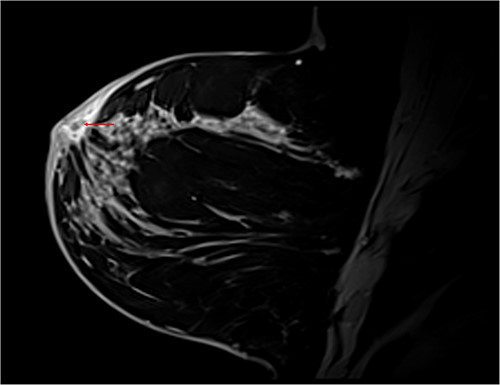

T1 Dixon sagittal MRI of the breast—changes restricted to the skin. Diffuse skin thickening of the periareolar region with small fluid collections (red arrow).

Differential diagnoses included granulomatous mastitis (GM) and inflammatory breast cancer (iPrevent score of 11.2% lifetime risk) [1]. A complete triple assessment was performed with bilateral breast imaging and core biopsy of the retroareolar lesion. Magnetic resonance imaging demonstrated benign breast changes and histopathology demonstrated suppurative chronic inflammation with granulation tissue and adjacent fibrosis without evidence of granulomas or malignancy (Fig. 4). Doxycycline was commenced with significant clinical improvement, supporting an HS diagnosis. The patient was discharged with ongoing multidisciplinary management involving a breast surgeon, an infectious diseases physician and a dermatologist.